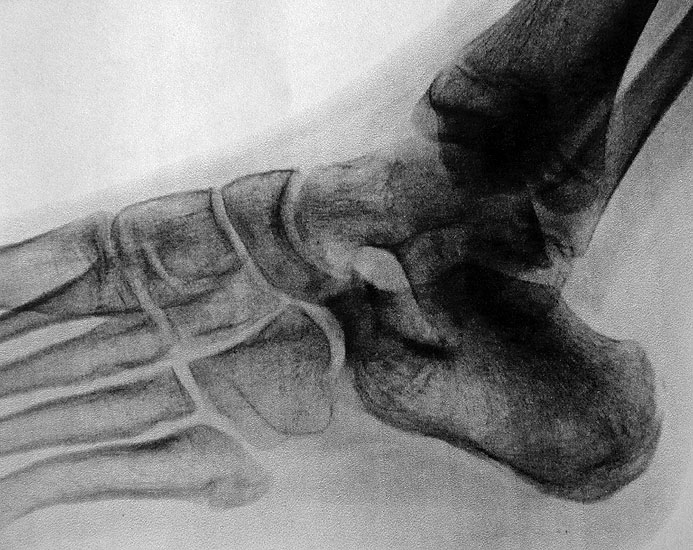

Die zweite wichtige Form tarsaler Coalitiones findet sich im medialen Bereich des Subtalargelenkes, am häufigsten unter Einbeziehung der medialen, mittleren Facette des talocalcanearen Gelenkes (Abb. 9). Die Ausdehnung der zunächst fibrösen, später zunehmend verknöcherten Brückenbildung kann sehr unterschiedlich Anteile der hinteren Kammer des unteren Sprunggelenkes mitumfassen; auch rein dorsomediale Formen ohne Einbeziehung der medialen Facette werden beobachtet (Abb. 2) 67 (Hamel 2008).

Diagnostisch sollte neben Röntgenübersichtsaufnahmen (indirekte radiologische Zeichen: Dorsaler Traktions-Osteophyt am Taluskopf, „talar beaking“; kontinuierliche Linie der Trochlea-tali-Kontur übergehend in die Sustentaculum-tali-Kontur, „C-Zeichen“ (Abb. 11) 10) immer die dreidimensionale Bildgebung eingesetzt werden. Das MRT (mit Kontrastmittel) kann die Struktur der Brückenbildung und z.B. die Qualität des Restgelenkes (Knorpel-Dicke) besonders gut abbilden; das Dünnschicht-CT zeigt die knöcherne Feinstruktur im Bereich der Coalitio und den oft sehr schrägen Spalt-Verlauf im Frontalschnitt dagegen häufig genauer. Meist findet sich die Überbrückung im Bereich der medialen Facette; die Schichten sollten jedoch bis weit nach dorsal beurteilt werden, da ansonsten dorsomediale Formen übersehen werden können. Rozansky et al 7 unterschieden fünf morphologische Typen auf der Basis von 3-D-CT-Rekonstruktionen. Allerdings ist eine prognostische Zuordnung bisher nicht möglich.